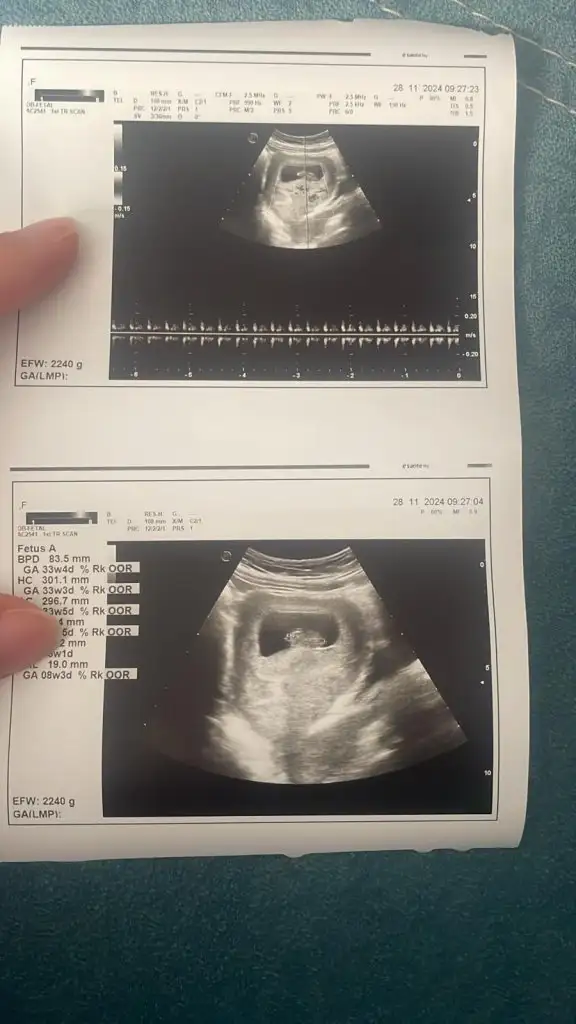

Kızlar yeni ultrason bu cinsiyet yorumu lütfen

• 61b6233d-55d3-4d1a-9ff5-c5eb16051583.webp

61b6233d-55d3-4d1a-9ff5-c5eb16051583.webp

31 KB · Görüntüleme: 53